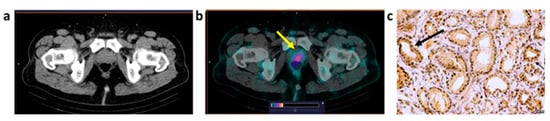

3.4. Imaging Data Analysis

3.5. Immunohistochemical Staining

| B1 | 34 | IC NST G2 | T2N0M0 | T: 1.41 (2.8 × 2.2) | 2.2 | T: 3+ | T2N0M0 |

| B2 | 41 | IC NST G2 | T2N2M0 | T: 1.75 (3.8 × 2.2) LNM: 1.8 (1.3) | T: 35 LNM: 16.3 | T: 1+ LNM: 2+ | T2N3M0 |

| B3 | 40 | IC NST G2 | T2N0M0 | T: 0.87 (5.1 × 2.2) LNM: 1.8 (1.4) | T: 10.8 LNM: 7.1 | T: 0 LNM:1+ | T3N3M0 |

| B4 | 69 | ILC G1 | T2N0M0 | T: 0.57 (6.8 × 3.2) LNM: 0.58 (2.5) | T: 7.8 LNM: 6 | T: 1+ LNM: 1+ | T2N1M0 |

| B5 | 56 | IC NST G2 | T2N1M0 | T: 0.87 (4.0 × 1.7) LNM: 1.8 (2.3) | T: 14.5 LNM: 11.3 | T: 0 LNM: 0 | T2N1M0 |

| B6 | 50 | IC NST G1 | T1N0M0 | T: 0.43 (1.5 × 1.5) | T: 4.3 | T: 3+ | T1N0M0 |

| B7 | 62 | IC NST G2 | T1N0M0 | T: 0.50 (1.5 × 1.4) | T: 2.7 | T: 1+ | T1N0M0 |